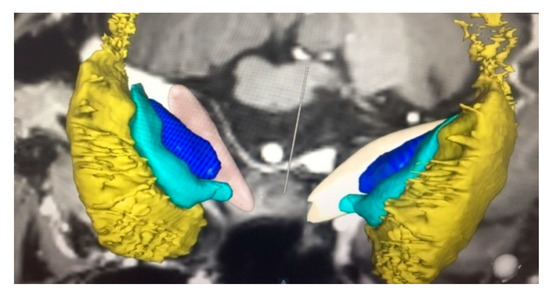

2.4. Operative Technique